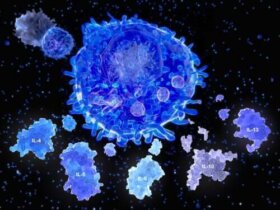

이 글에서는 “사이토카인 폭풍”으로 알려진 드문 현상과 우리 몸이 때때로 자기 자신과 싸우는 이유에 관해 살펴보도록 하자. 일부 국가의 코로나바이러스…